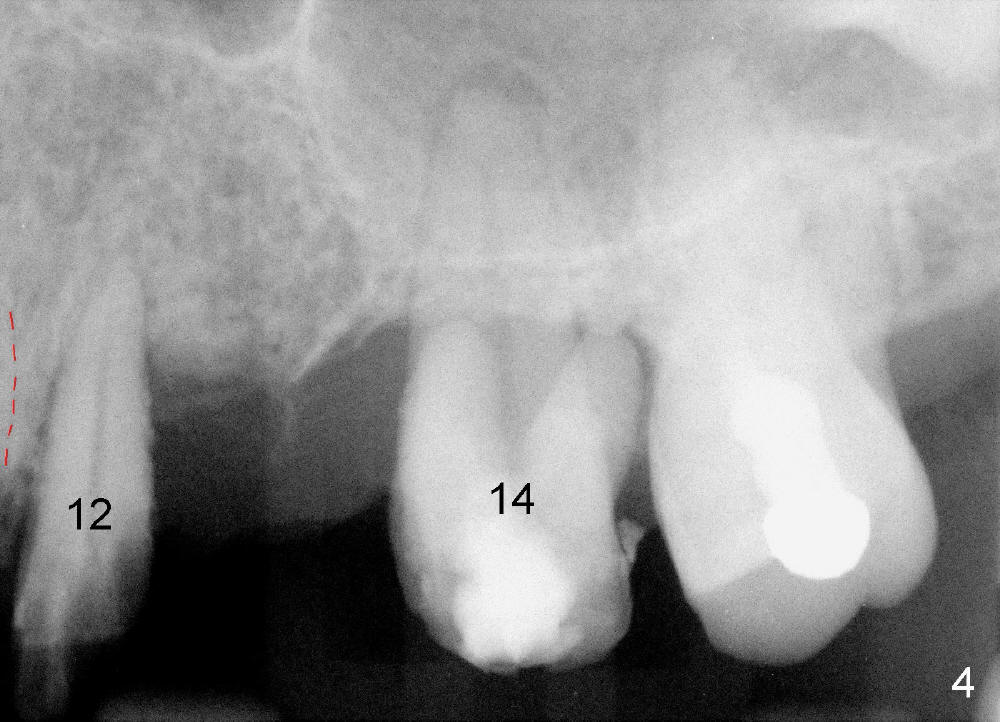

A 53-year-old lady has a failing bridge (Fig.1). There is severe bone loss around the buccal roots of #14 (*). Purulent discharge is from the gingival sulcus (Fig.2 <) with localized gingival erythema and edema (*). When the bridge is removed, the tooth #12 is found nonsalvageable (Fig.3,4). These two teeth are to be replaced by immediate implants (Fig.5). Although the sinus floor is low buccally (arrowheads), a 6x14 mm gingiva-level implant can be placed in the septum close to the palatal socket or in the palatal socket at the site of #14.

Placement of immediate implant at the site of #12 is relatively easy. Adjustment is more or less mesiodistal. A 2 mm pilot drill (Fig.6 P) is found close to the root of the tooth #11 (red dashed line). The osteotomy is then moved distally (Fig.6 arrow). When 4.5x20 mm tap (Fig.7: #12) and 4.5x17 mm implant (Fig.8 I) are placed, there is distance from the root of the neighboring tooth. Insertion torque of the both implants is >60 Ncm. Abutments are placed (A in Fig.8) for immediate provisional.